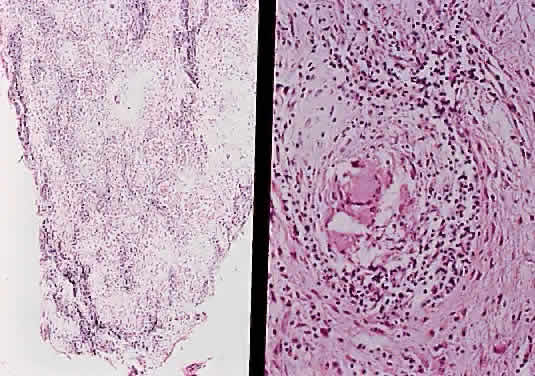

Fig. 37. Pilocytic glioma of optic nerve (hematoxylin and eosin staining). Low power on left shows nerve surrounded by thickened meninges. High power on right shows spindle-shaped cells.

Two histologic features that are present in nearly every example of pilocytic astrocytoma are Rosenthal fibers and eosinophilic granular bodies. Rosenthal fibers are enlarged, brightly eosinophilic cell processes that are sausage or corkscrew-shaped. On Masson trichrome staining, they are bright red (Fig. 38). Ultrastructurally, Rosenthal fibers are defined by amorphous aggregates of electron-dense material within the nerve processes. The number of Rosenthal fibers in different tumors and even within an individual tumor varies considerably; rarely, they are absent entirely. Granular bodies, as the name suggests, consist of rounded eosinophilic proteinaceous structures (Fig. 39). Neither Rosenthal fibers nor granular bodies are unique to pilocytic astrocytomas and are commonly seen in other low-grade astrocytic neoplasms (e.g., ganglioglioma). Their presence, however, essentially excludes a high-grade glioma.